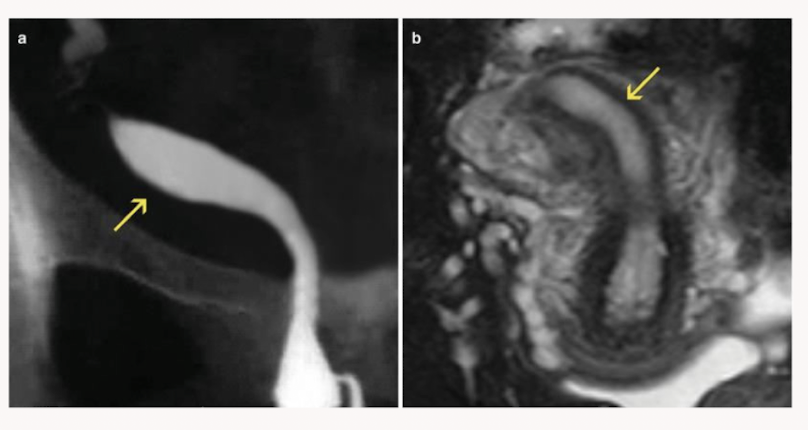

Septate uterus: A single wide fundus but with two uterine cavities (septum in the middle)

The septum is only partially dividing the uterine cavity. Name the uterine anomaly

Subseptate uterus